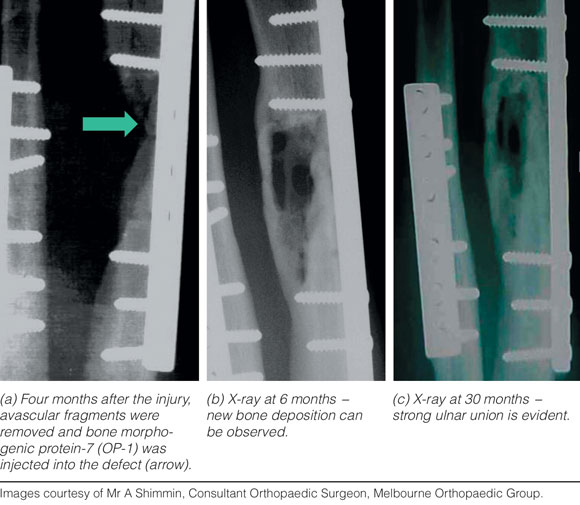

In 2002, it was shown that injecting recombinant human OP-1 into a bone non-union site resulted in healing of the non-union after 30 months.8 OP-1 acts by recruiting adult osteogenic precursor MSCs to repair the bone defects (Box 1). In an Australian study of 163 consecutive patients, including 113 patients with long bone fracture and in whom non-union occurred, OP-1 was used at a mean of 23.2 months after injury, with a follow-up of 19 months. Clinical bone union was achieved in 70% of patients, and radiological bone union in 65%; 35% of these patients had previous failed bone autografts. No significant adverse reactions were attributed to the OP-1 implant. There was also a decreased incidence of osteomyelitis at the surgical site, and bone donor site pain was eliminated, as reflected in decreased use of postoperative analgesia.8